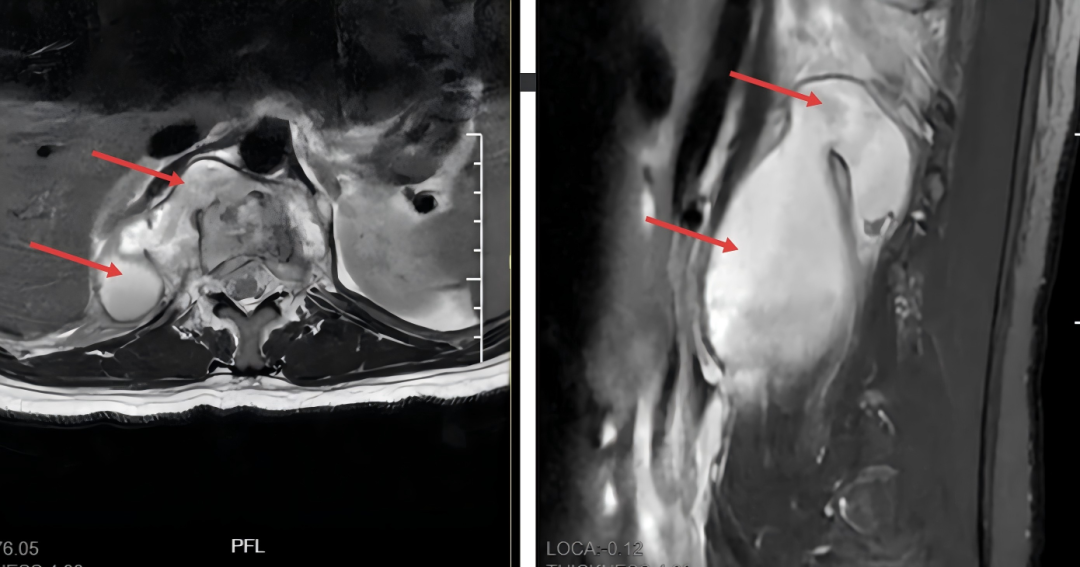

图为部分脊柱结核患者拖延病情后所导致的严重骨质松懈(上图椎体虫蚀样骨松懈)和宏大椎旁脓肿病灶(下图箭头)!经过多学科团队合营,kaiyun sports以上病例均得到直率疗养并病愈。